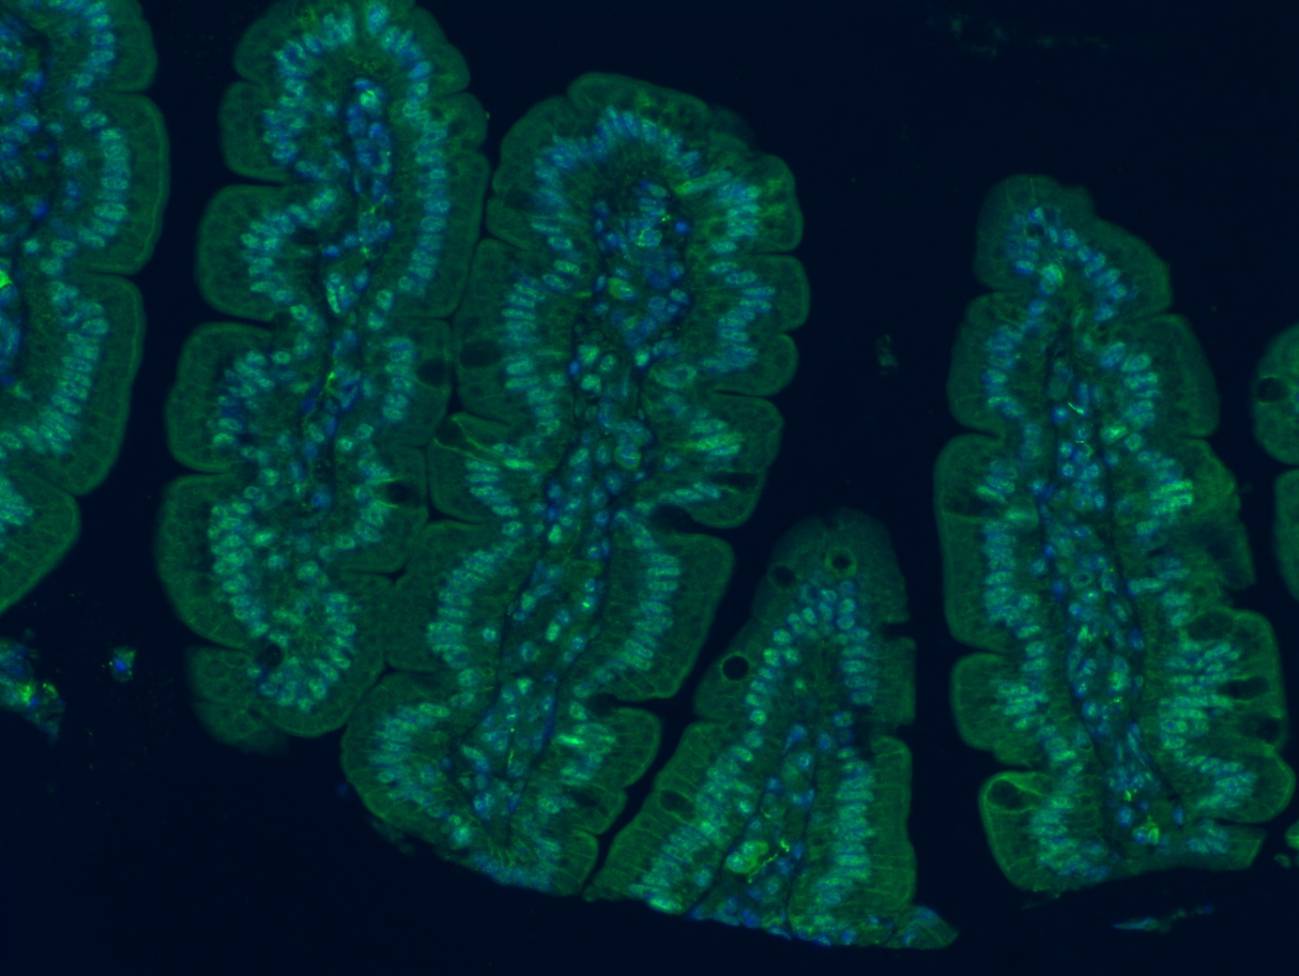

Inmunofluorescencia del tejido intestinal de ratón en la que se observa la proteína p‑LKB1, implicada en procesos celulares relacionados con la función intestinal. / Wikimedia Commons